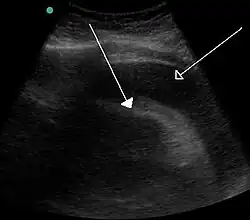

A very large hemorrhagic pericardial effusion due to malignancy as seen on ultrasound which was causing tamponade. closed arrow: the heart, open arrow: the effusion

Tamponade (/ˌtæm.pəˈnd/[1]) is the closure or blockage (as of a wound or body cavity) by or as if by a tampon, especially to stop bleeding.[2] Tamponade is a useful method of stopping a hemorrhage. This can be achieved by applying an absorbent dressing directly into a wound, thereby absorbing excess blood and creating a blockage, or by applying direct pressure with a hand or a tourniquet. Not to be confused with a tamponade that occurs as a result of health problems. For example: cardiac tamponade is a condition where fluid collects in the pericardial sac increasing pressure within the pericardium which in turn prevents the ventricles from expanding fully significantly reducing the efficiency of the heart. It is considered a medical emergency and if left unchecked is fatal.